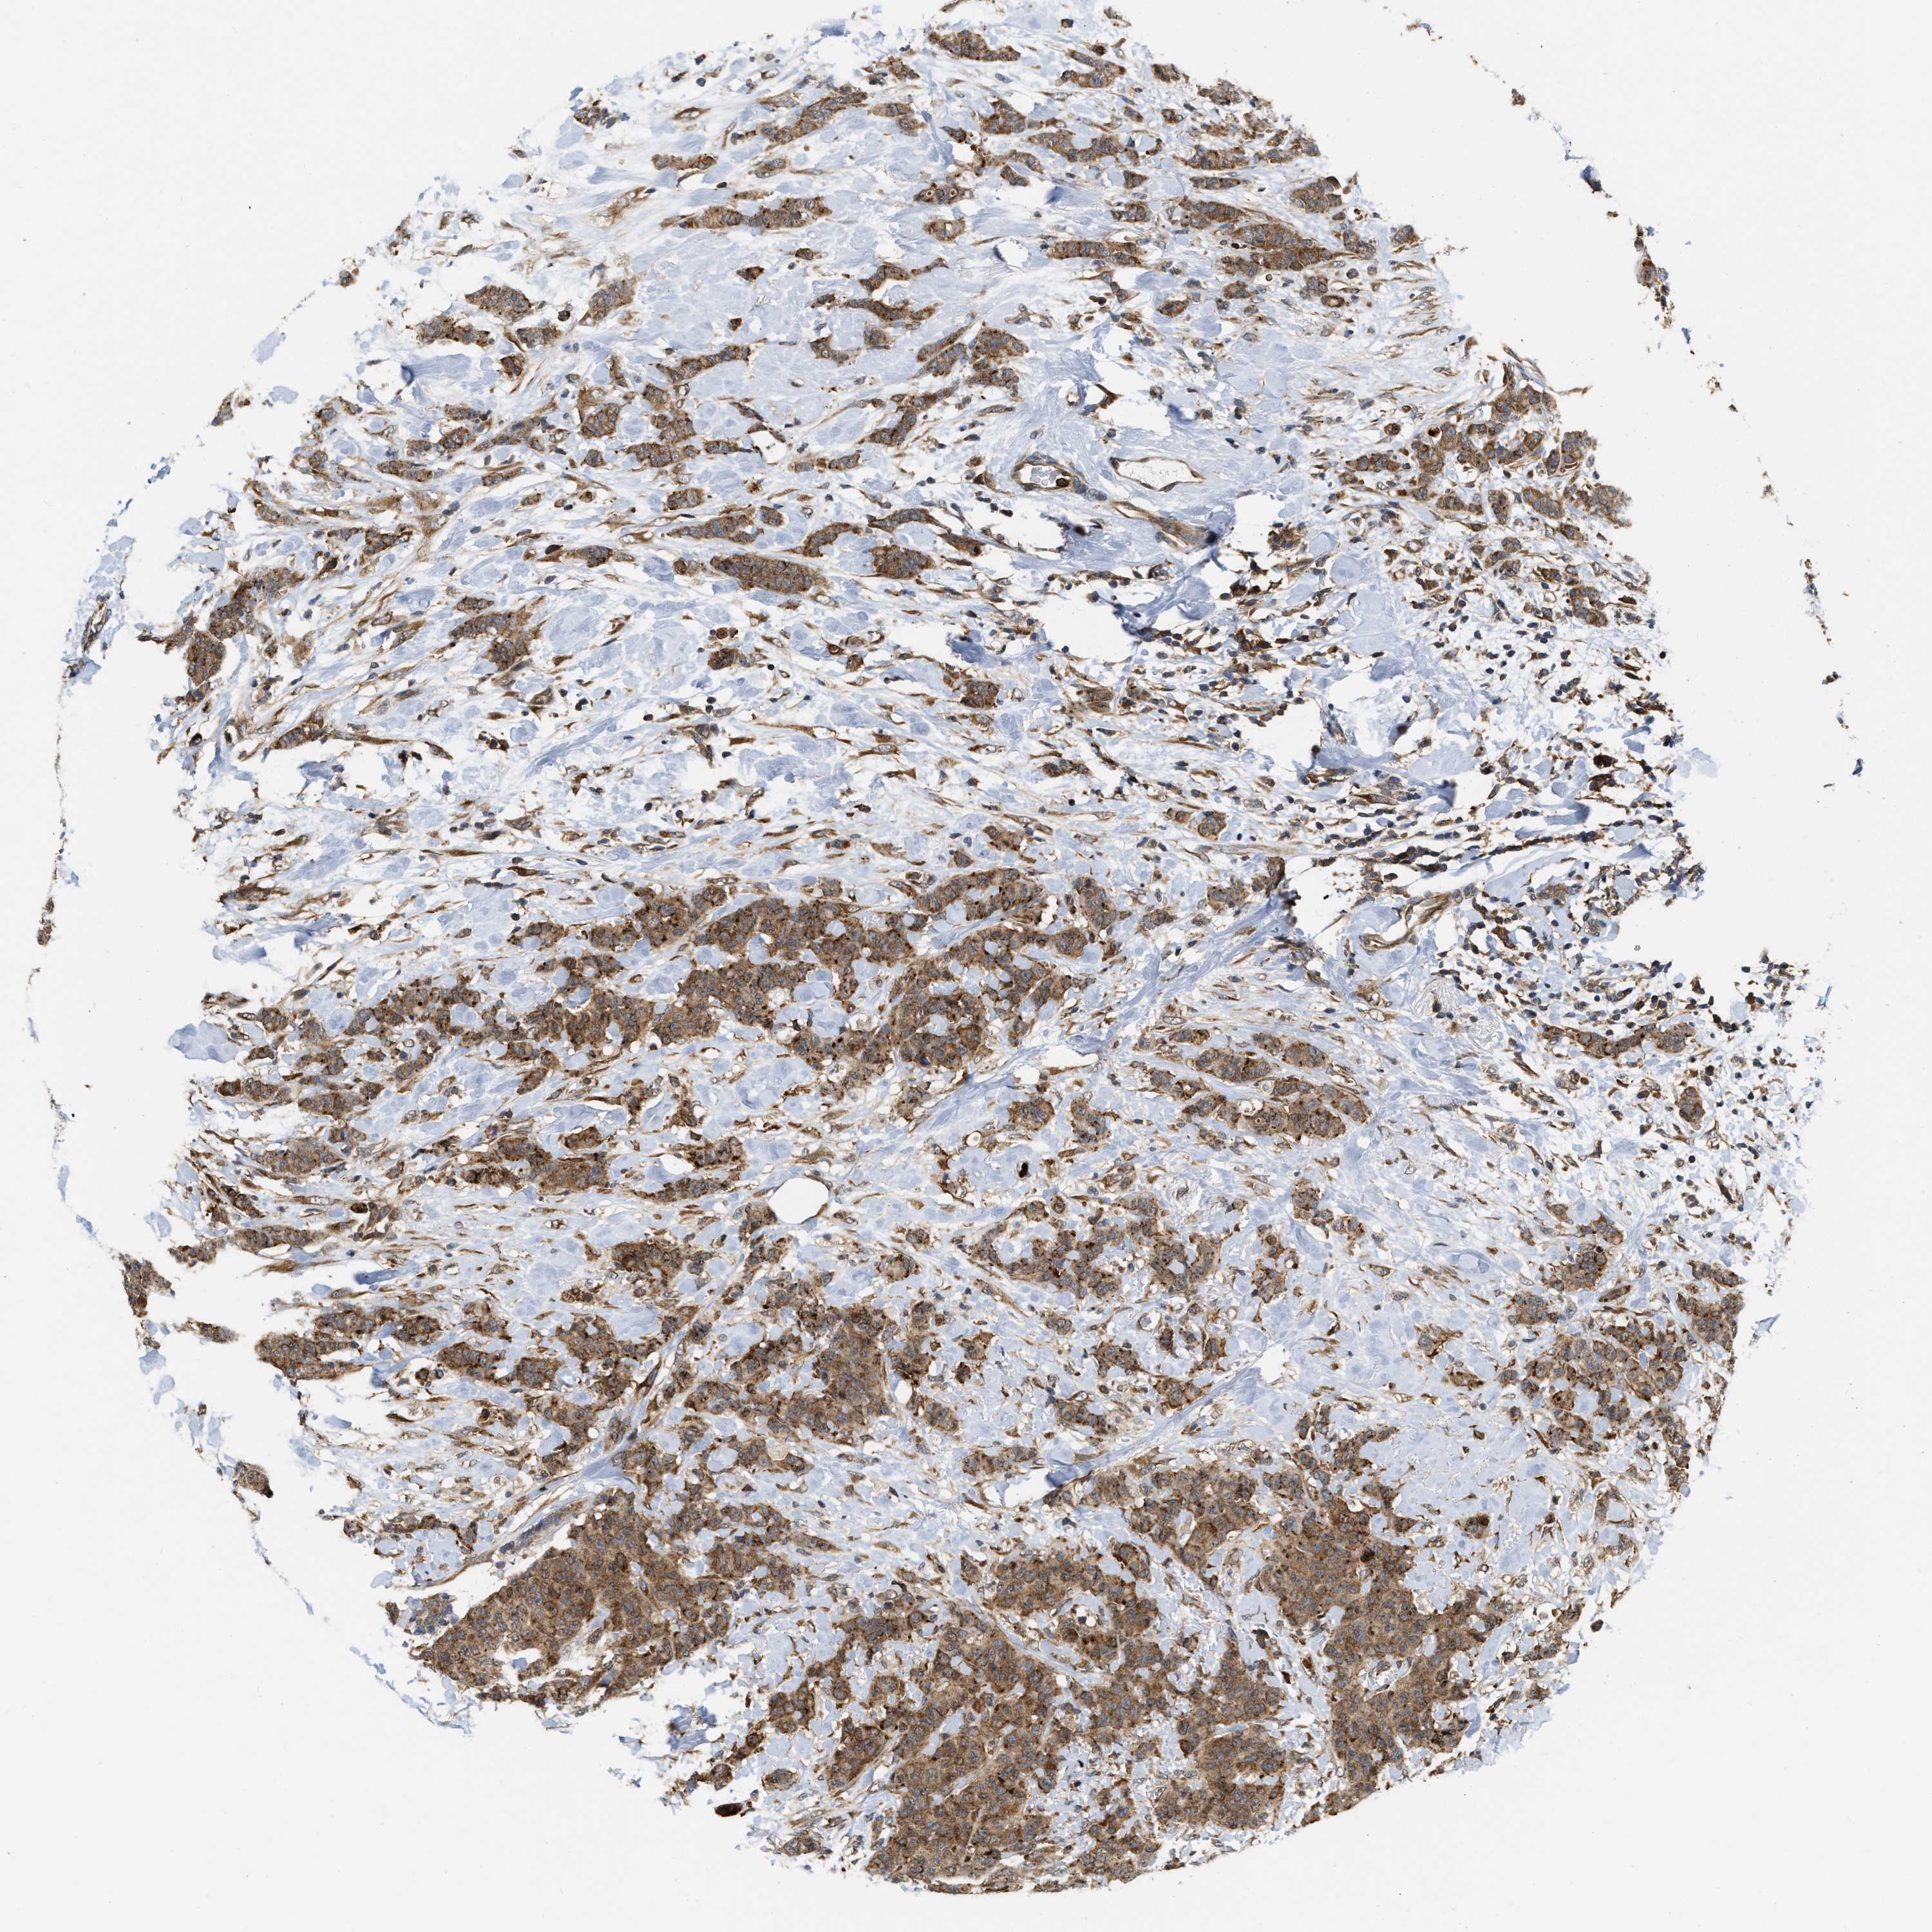

CANCER BREAST CANCER Show tissue menu

BRCA TCGA BRCA VALIDATION PROTEIN EXPRESSION